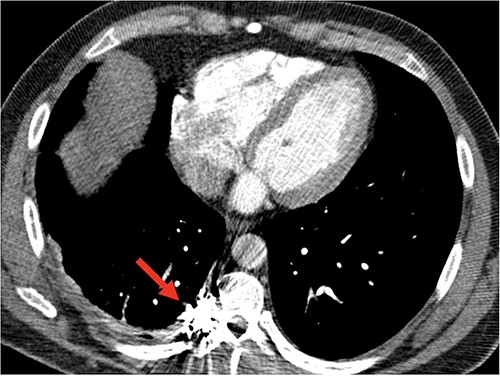

A 41-year-old adult with NF1, presented with a spontaneous right-sided hemothorax after strenuous exercise associated with a presyncopal episode at home. A CT chest angiogram revealed a moderate-to-large right side hemothorax and a 13-mm fusiform aneurysm of the right posterior T9 intercostal artery without active extravasation (Fig. 1A and B). Due to concern for aneurysmal rupture, he was transferred to a tertiary care center.

(A) Axial CT with contrast demonstrating a large right hemothorax on presentation; (B) sagittal CT with contrast, arrows showing T9 intercostal artery aneurysm.